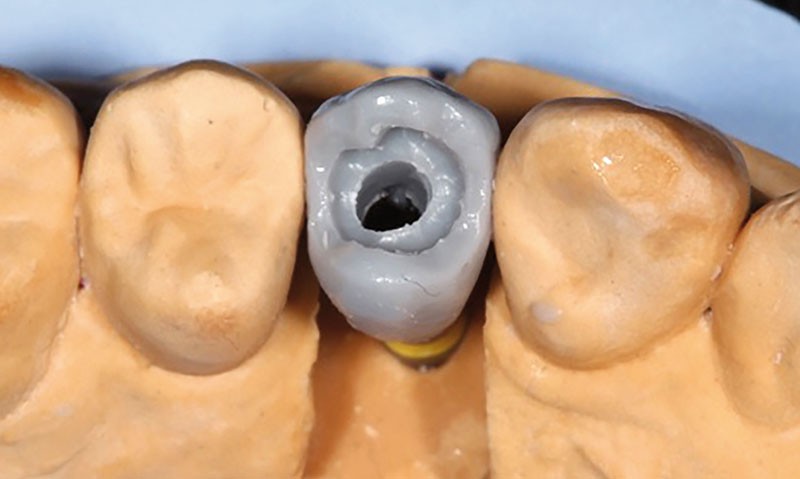

Après la confection des modèles de travail et transfert en articulateur, le prothésiste dentaire choisi l’embase titane (Variobase®, Straumann) correspondante au diamètre implantaire et à la hauteur prothétique disponible. Ces Variobases sont modifiables au laboratoire uniquement si une réduction de hauteur s’impose.

Dans un premier temps, le prothésiste réalise une maquette en cire de la restauration sur l’embase titane (fig. 2).

Elle est ensuite pressée. Pour notre patient, après le relevé de couleur des dents adjacentes, c’est un lingotin LT, IPS e.max® (Ivoclar Vivadent) qui est choisi. La céramique cosmétique est ensuite maquillée et glacée. Le protocole du fabricant est rigoureusement suivi. Cette céramique est perforée au niveau du puits de transvissage implantaire permettant l’assemblage sur l’implant. Dans un second temps, après sablage de la partie supérieure de la Variobase® et de l’intérieur de la pièce en céramique pressée, les deux pièces sont solidarisées avec une colle spécifique : le Multilink Hybrid Abutment® (Ivoclar Vivadent). Afin d’éviter des erreurs de positionnement, l’assemblage est réalisé directement sur le modèle. Dans un troisième temps, un « bouchon » ou « plug », est élaboré en cire, directement…